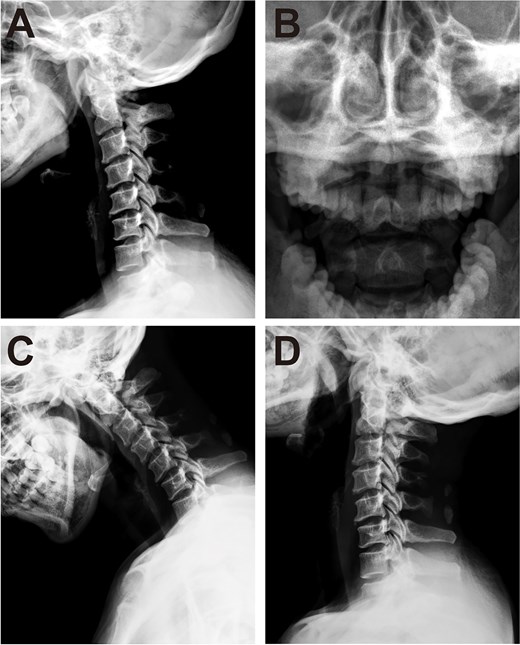

Cervical radiographs revealed hypoplasia of C1 but no evidence of atlantoaxial dislocation (Fig. 1). CT scans indicated bilateral bone abnormalities on the lateral sides of the posterior arch, particularly on the left side, with a midline cleft of the anterior arch (Fig. 2A). Three-dimensional reconstruction further demonstrated this abnormality (Fig. 2B–D). T2-weighted MRI revealed an intramedullary high signal at the C1 level, but no compression of the cord was observed (Fig. 3A and B). Cervical flexion-extension imaging indicated minor stenosis of the upper cervical spinal cord in the neck flexion position, but this alteration was not substantial (Fig. 3C–F). We considered that the high signal may be related to the repeated subtle activity of the posterior atlantoaxial arch in the past over a long period of time.

Cervical spine radiograph. (A) Lateral radiograph demonstrating partial aplasia of the posterior arch of the atlas. (B) Open-mouth radiograph showing no atlantoaxial dislocation. (C, D) Cervical spine dynamic X-ray.